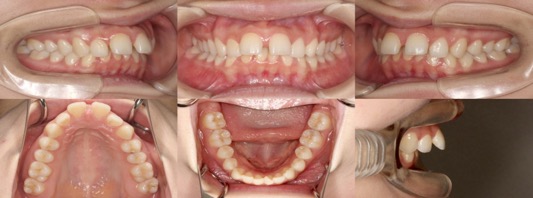

為您介紹隱適美矯正的治療案例。

※案例圖片著作權:隱適美醫師網(禁止轉載)

從案例照片的矯正前後對比中,可以清楚地看出其效果。